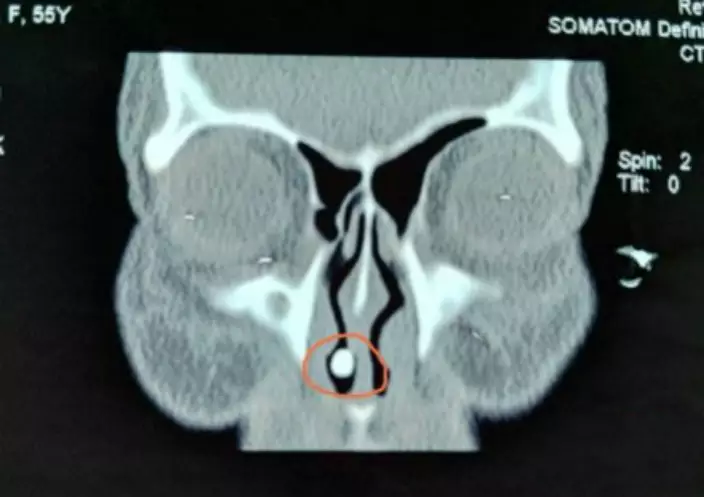

57歲的夏女士已經忘記自己何時開始出現流鼻血及鼻塞的情況,但當時以為自己只是熱氣或鼻敏感,所以並無求診。但直到最近,流鼻血及鼻塞的情況更加嚴重,還會感到痛楚,便到湖南省人民醫院求診,卻被告知鼻腔內生了一隻長18毫米的牙齒!

該醫院耳鼻咽喉頭頸外科醫生周建波經過初步檢查,確診為鼻內異物,但初時懷疑夏女士只是不小心吸入異物,醫生卻在手術中發現鼻腔內的白色異物不論是形狀或是質地都與牙齒相似。醫生成功將異物取出後,竟然取出一個長18毫米,闊5毫米,更有牙根及牙冠的完整牙齒。

周醫生表示,該牙齒屬於多生齒,是患者在胚胎發育時發生變異而導致,而目前國內文獻報道只有不到20宗相同病例。口腔科醫生陳文玉指,異位多生齒在上頜竇(Maxillary Sinus)的情況比較常見,而生在鼻腔內的情況是非常罕見。